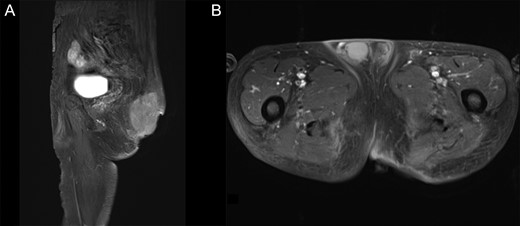

A 74-year-old male presented to our institution with soft tissue sarcoma in the left gluteal region and bleeding from the tumor (Fig. 1A). The perianal tumor was 15 cm in size. Redness, exudation and fetid odor were observed, and the patient exhibited poor mobility compared to baseline. Although the Eastern Cooperative Oncology Group Performance Status was 0 [2], the patient was unable to tolerate the supine position due to the giant tumor mass and also required assistance for defecation. On contrast-enhanced MRI, a tumor with fatty component was revealed primarily inside the left gluteus maximus muscle (Fig. 2A and B). On culture examination, Streptococcus gallolyticus, Bacteroides fragilis and Enterococcus avium were identified from the wound exudate, which was suggestive of an infection concurrent with the tumor. The needle biopsy indicated a spindle cell tumor with positive immunostaining for MDM2 and Cdk4. Based on these findings, the left gluteal region was diagnosed as dedifferentiated liposarcoma with wound infection and American Joint Committee on Cancer Stage III (T2bN0M0, high grade).

T1WI contrast-enhanced MRI with fat suppression at first visit. (A) Sagittal image. (B) Axial image. Left gluteal region: a 15 cm tumor extending from the gluteus maximus muscle to the subcutaneous tissue with enhancement of irregular margins was observed. A portion of the tumor had disintegrated, and the internal mass was heterogeneous.